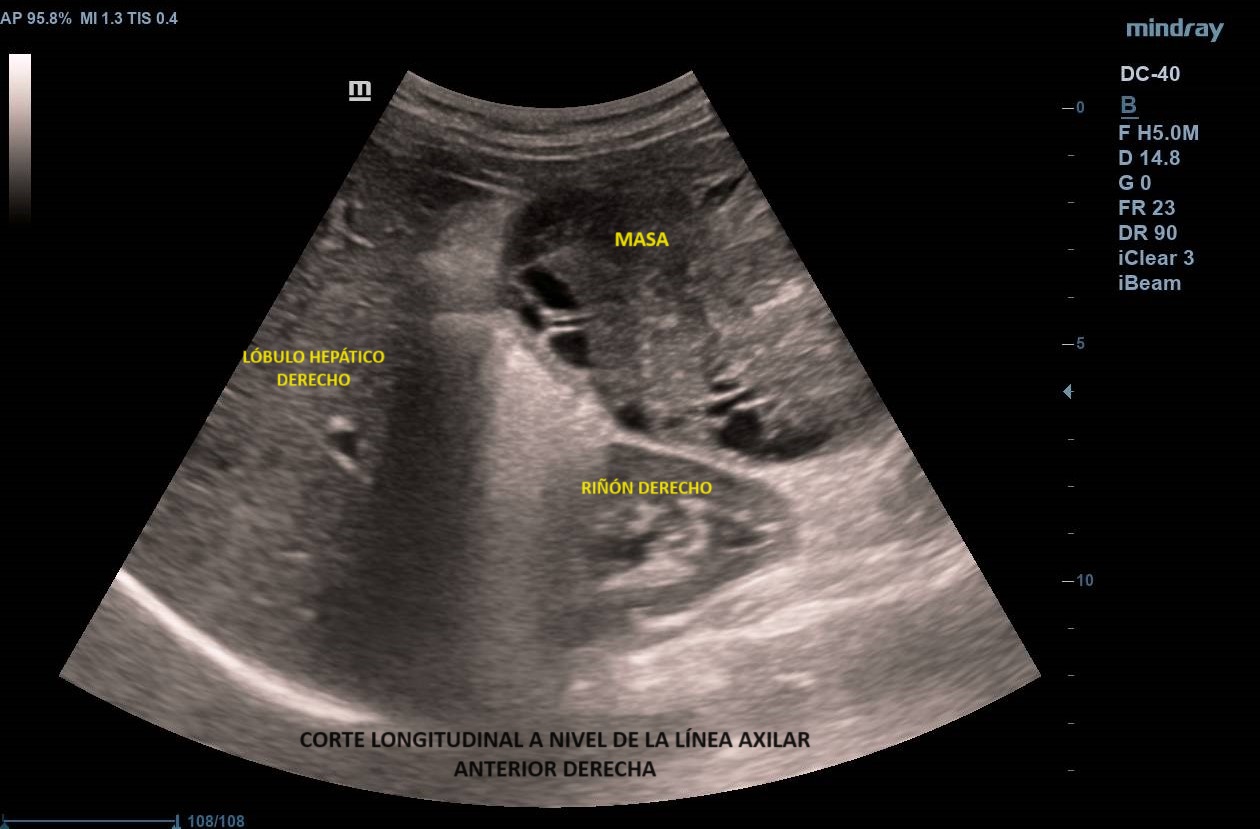

Exploración física: Abdomen: Difícilmente depresible a la palpación con presencia de masa que ocupa todo el abdomen, levemente doloroso en flanco derecho. No signos de irritación peritoneal.

Ecografía abdominal clínica: Masa heterogénea que ocupa todo el abdomen, de aspecto sólido, vascularizada con zonas hipoecoicas-anecoicas en su interior. Riñones con eco-estructura sin alteraciones, hígado sin LOES. Vejiga sin engrosamiento de paredes, útero parcialmente visible. Anejos y retroperitoneo no valorables. No líquido libre.

Se deriva a urgencias donde realizan ecografía transvaginal confirmando presencia de masa que parece depender de anejo derecho. Solicitan TAC toraco-abdomino-pélvico objetivando «masa abdominal gigante de dudosa dependencia ovárica, no pudiendo descartar liposarcoma abdominal». Citan a la paciente para RM donde se demuestra contacto pero no dependencia de masa abdominal, probable liposarcoma, de anejo derecho, de características normales. Analítica con marcadores tumorales sin alteraciones.